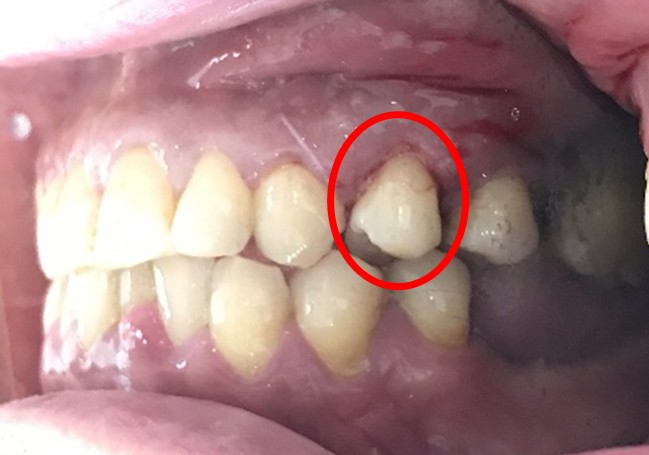

ブリッジの支台になっている奥の歯が、被せ物の中で虫歯になり、支台の役割を果たさず、前方の歯のみで支えられていました。前方の歯をそのままにして、後方の部分を切り離すと、そのまま取れてきました。中は、虫歯で歯根しか残っていない状況でした。この歯は、根管治療後、単独でオールセラミック冠を被せ、歯のないところにインプラントを埋入しました。

Before

冠の中で大きな虫歯になり支台の役割を果たしていませんでした。

【インプラント埋入前】

冠はブリッジを切断しただけで取れてきました。軟化象牙質を取り除いたところ、歯根しか残っていない状況で保存できるかどうかのぎりぎりのところでした。